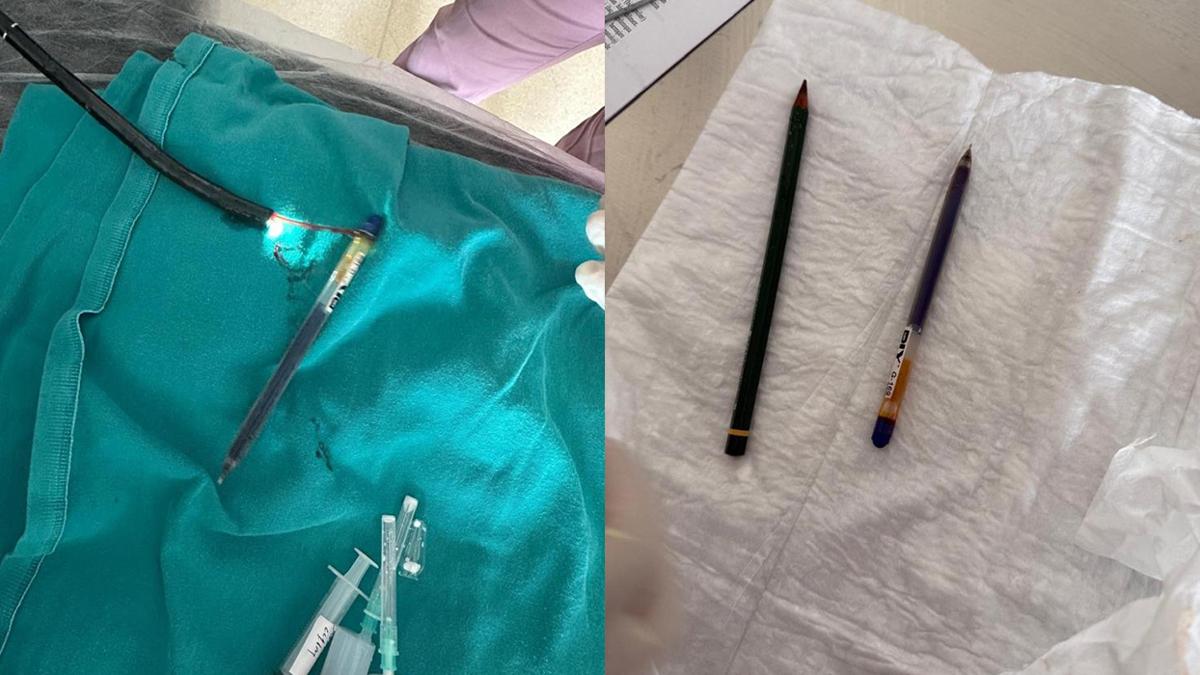

Ağrı'da OKB rahatsızlığı olan genç kadın, kalem yutma şikayetiyle hastaneye kaldırıldı. Yapılan endoskopi işleminde kadının midesinden biri kurşun, diğeri tükenmez olmak üzere iki kalem çıkarıldı.

Ağrı'da Obsesif Kompulsif Bozukluk (OKB) rahatsızlığı bulunan 22 yaşındaki kadın, kalem yutma şikayetiyle hastaneye kaldırıldı. Ailesi tarafından Ağrı Eğitim ve Araştırma Hastanesi Acil Servisi'ne getirilen hastanın midesinde yabancı cisim tespit edildi. Genel Cerrahi ekibince ertesi gün gerçekleştirilen yaklaşık bir buçuk saat süren endoskopi operasyonuyla genç kadının midesinden biri kurşun, diğeri tükenmez olmak üzere iki kalem çıkarıldı. Başarıyla sonuçlanan operasyonun ardından hasta bir gün müşahede altında tutularak taburcu edildi.

Operasyonu gerçekleştiren Dr. Öğretim Üyesi Adem Aslan, ilk kez böyle bir vakayla karşılaştıklarını belirterek, "22 yaşındaki bayan hastamız kalem yutma şikayetiyle ilçe devlet hastanemize başvurmuştu. Tomografisinde midesinde yabancı cisim olduğu görüldü. Biz de tetkiklerimizde midesinde kalem olduğunu gözlemledik. Daha önce toplu iğne, kemik parçası gibi yabancı cisimlerle karşılaşıyorduk ama bu kadar uzun ve ince bir cisim ilk kez karşımıza çıktı. Midenin boşalması için bir gün bekledik ve ertesi gün yaptığımız endoskopide hastanın bir değil iki kalem yuttuğunu gördük. Yaklaşık bir buçuk saat süren işlemde kalemleri endoskopik yöntemle çıkardık. Hastamızın Obsesif Kompulsif Bozukluğu olduğu için ailesine yalnız bırakmamalarını ve bu tür cisimleri ortalıkta bulundurmamalarını tembih ettik. Bir gün müşahede altında tuttuktan sonra şifa ile taburcu ettik" dedi.